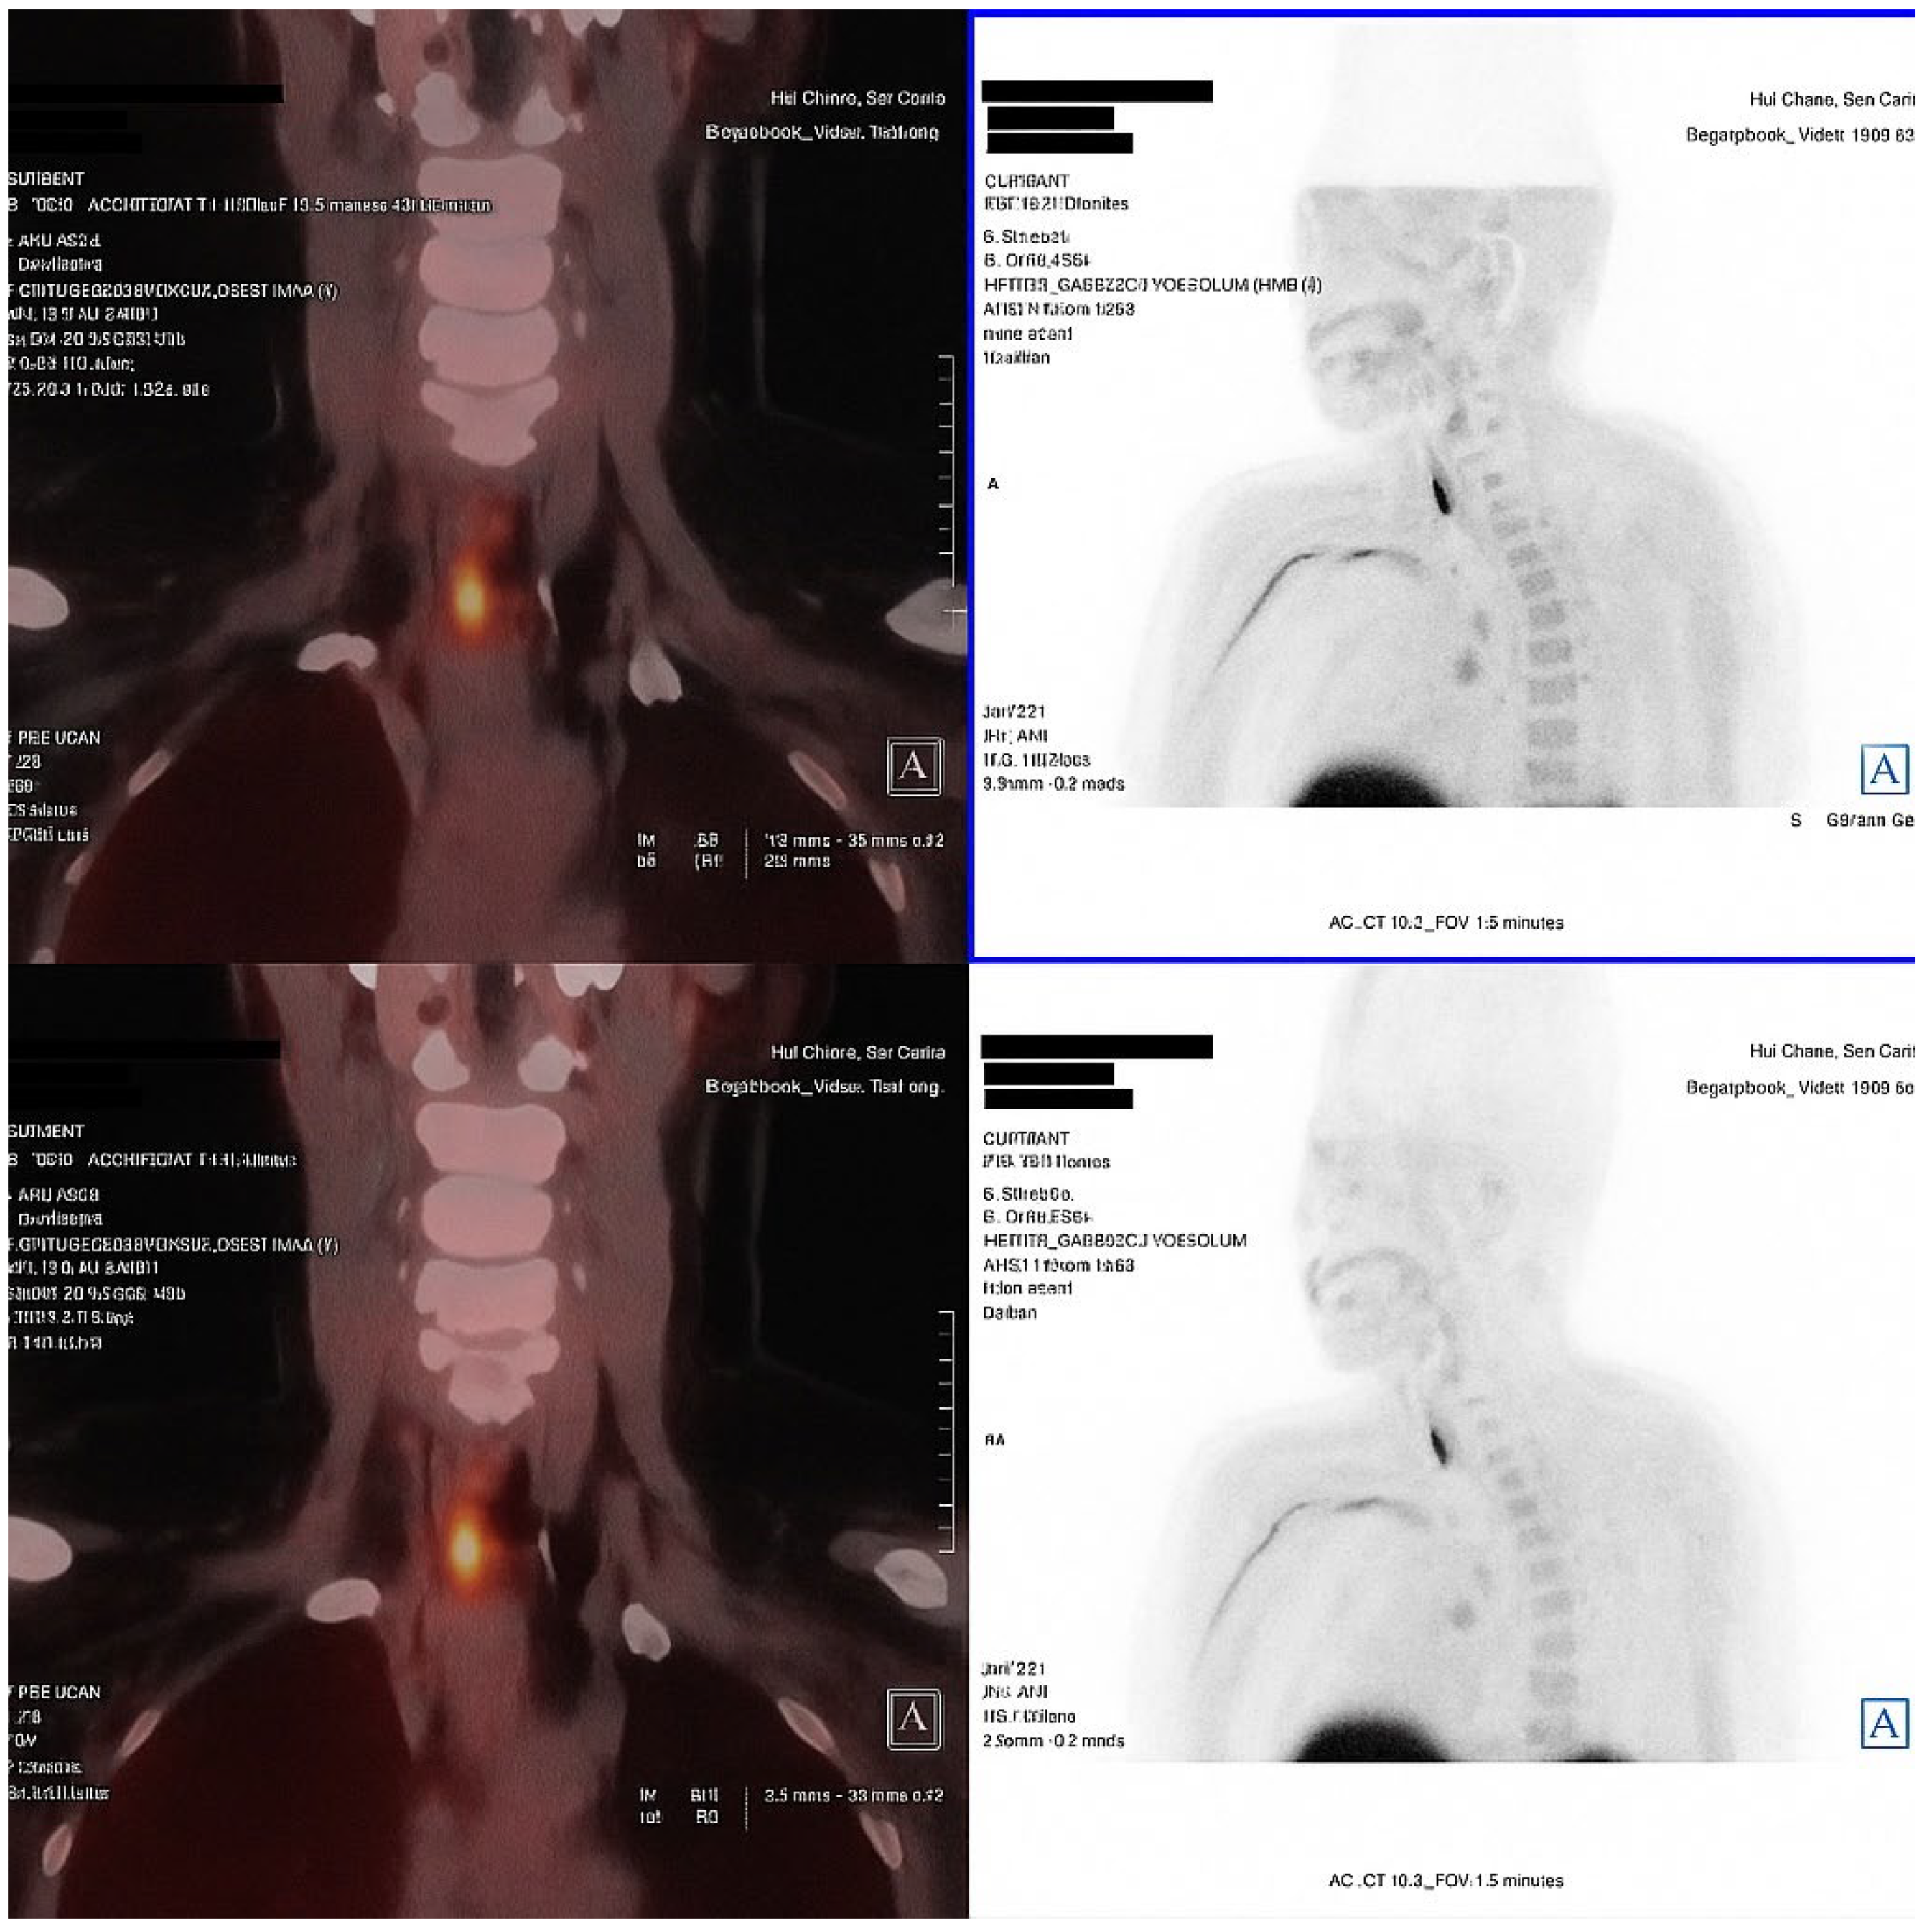

An 18F-fluorocholine PET-CT (18F-choline PET-CT) scan performed in November 2024 identified two right parathyroid adenomas, located in the upper and lower poles. The patient did not report renal colic, falls or new fractures. At the most recent follow-up, a diagnosis of PHPT was confirmed, characterized by hypercalcemia, persistent hypophosphatemia, elevated PTH and FGF-23 levels and absence of hypercalciuria or overt hyperphosphaturia.

Secondary causes of hyperparathyroidism, including vitamin D deficiency, chronic kidney disease, and malabsorption, were excluded, thereby supporting the diagnosis of primary hyperparathyroidism (PHPT) (Figure 1).

In this case, hypophosphatemia was an early biochemical finding that persisted for nearly a decade, preceding the development of the classic biochemical profile of primary hyperparathyroidism. The patient was referred for surgery.

Figure 1. Fused coronal and axial images (left) and anterior projection MIP sections (right) identify two areas of focal increased uptake in the right cervical region. The uptake corresponds to a posterosuperior nodular lesion and an inferoposterior nodular lesion adjacent to the right thyroid lobe, findings consistent with double right parathyroid adenomas (superior and inferior). This technique localized the parathyroid adenomas, eliminating the need for FDG-PET to exclude oncogenic osteomalacia.